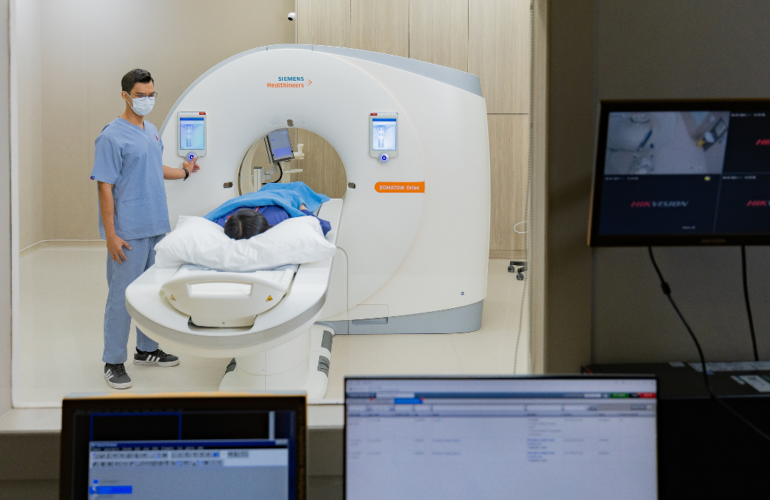

Cardiac Computed Tomography (CT) Scan: A Comprehensive Guide for Your Heart Health

A cardiac CT scan is a powerful tool for diagnosing heart conditions, from coronary artery disease t…